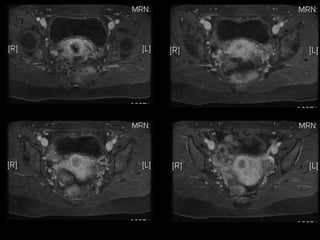

HISTORY โ€ข 42 yo female โ€ข Recent immigrant from China โ€ข C/O postcoital and intermenstrual bleeding โ€ข Abnormal GYN exam โ€ข Abnormal biopsy โ€ข Further imaging performed

MRI findings -Stage IIB with PET/CT - Stage IIIB Cervical Cancer

Role of MRImaging in Tx Stratification of GYN (Cervical) Cancer โ€ข Cervical Cancer โ€“ 2nd most common ca in women worldwide โ€“ Developing countries; pk 30-40 yrs โ€ข FIGO classification โ€“ revised in 2009 from just clinical to incorporate cross-sectional imaging (CT, MR) โ€ข Staging accuracy of MR 85-96% โ€“ Best test to assess tumor size and location; invasion into parametria, pelvic side wall, adjacent organs; local nodal enlgment โ€ข PET/CT helpful in staging advanced disease โ€“ Demonstrates unexpected sites beyond pelvis โ€ข Treatment options โ€“ Radical surgery - early stage (IA, IB1, IIA1) โ€“ Primary Chemo and Radiation โ€“ bulky IB2 or IIA2, or local advanced (IIB or greater) Sala et al. Radiology 2013; 266: 717.